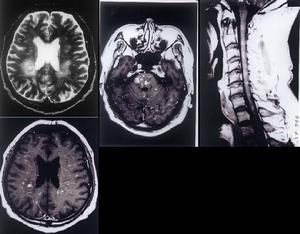

神經系統也是本病常見的受累部位。屍解發現腦膜血管和腦實質有典型性且具有漿細胞樣多形細胞廣泛浸潤在廣泛壞死區內可見有神經細胞喪失和白質碎裂,也可見有腦血管局灶性阻塞伴管壁壞死,管壁呈非典型性淋巴網狀細胞浸潤血栓形成,管腔狹窄和動脈瘤形成。部分死亡病例屍解時尚可見腦和脊髓內有廣泛性壞死區,可伴有免疫母細胞肉瘤,個別病例屍解時發現中腦和腦橋有廣泛壞死,其腦組織由非典型性淋巴組織細胞所取代。

2.神經系統 表現有周圍神經病腦神經麻痹和各種中樞神經系統症狀及體徵。神經系統受累時可出現失語、頭痛、感覺異常偏癱、共濟失調、精神錯亂抽搐等。可發生於肺病變以前、中間、甚至肺部病變緩解時。周圍神經病變多為非對稱性中樞神經系統病變可累及腦和脊髓的任何部位可出現Bell麻痹、暫時性失明復視突眼視力下降或眩暈;常見症狀包括失語、輕偏癱失明運動失調、截癱、動眼神經麻痹、腦神經麻痹、頭痛感覺異常、意識模糊昏迷抽風四肢癱視神經水腫、耳聾面癱感覺遲鈍、腦水腫腦膜腦炎等。周圍神經受累出現下肢感覺異常。可發生在其他系統病變出現之前,甚至當肺內病變在不斷消退緩解時中樞神經系統病變仍可在不斷發展。一個患者多發生上述症狀中的一種或數種神經系統病變的發生與預後直接相關一旦神經系統受累,其死亡率高達80%以上。

併發症: 最常見的併發症為呼吸困難,尤其見於縱隔或肺的淋巴結腫大者臨床病情與淋巴瘤相似的患者,約1/3可出現肺空洞,可因大咯血而死亡。也可發生肺葉支氣管部分阻塞肺實質大片破壞引起呼吸衰竭也是本病的主要死亡原因。中樞神經系統病變可累及腦和脊髓的任何部位,可出現失語輕偏癱失明、運動失調截癱動眼神經麻痹腦神經麻痹、頭痛感覺異常、意識模糊昏迷、抽風四肢癱視神經水腫耳聾、面癱感覺遲鈍腦水腫腦膜腦炎等廣泛浸潤肝臟,可造成進行性肝功能衰竭而死亡。屍解發現肝、脾、淋巴結腎、心臟和胃腸道均可受侵犯。